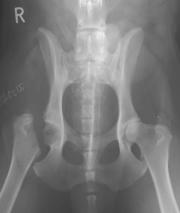

Клинические проявления дисплазии Диагностика Лечение До недавнего времени считалось, что кошки не подвержены дисплазии тазобедренных суставов (ДТБС). Это заболевание широко распространено среди многих пород собак как наследственная аномалия. По новым сведениям, оказалось, что эта болезнь встречает...